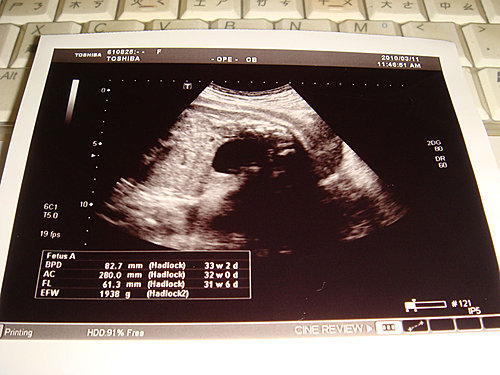

但是,超音波照出來的結果,寶寶的體重只比上週多了67公克,真不知我吃的東西都長去那裡了,不過醫生說,寶寶本週的位置不好照,所以可能會有誤差,希望小圓的體重快快破二千呀!而小圓現在還是胎位不正,但醫生說有機會轉回來,所以要我持續做胎位的運動,小圓,我們一起加油吧!

BPD→頭的橫徑,82.7mm ,33w2d

AC →腹圍長度,280.0mm ,32w0d

FL →大腿骨的長度,61.3mm ,31w6d

EFW→Baby透過超音波量體重,預估約1938g